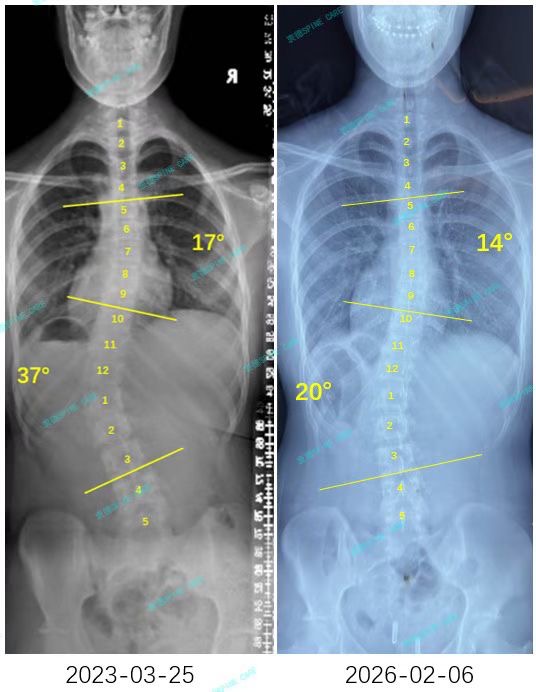

来自家长对衷德的评价(小欣妈妈)